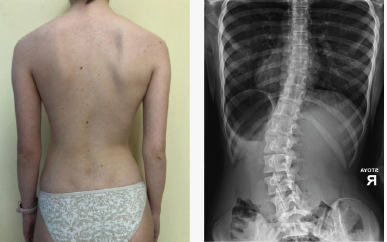

Сколиоз 2 Степени Фото Лечение